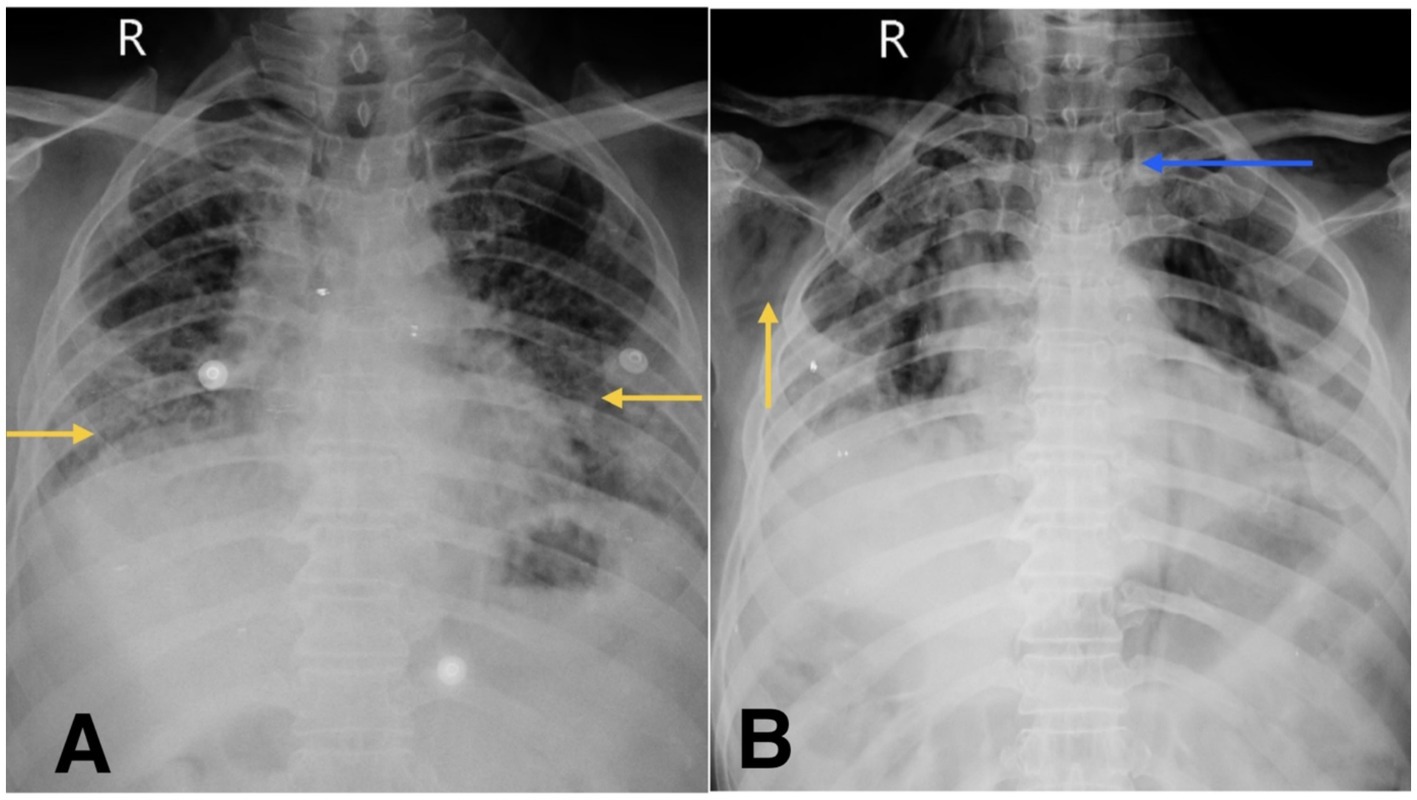

He was admitted to the respiratory medicine department and transferred to the intensive care unit (ICU) for close monitoring. Chest radiography revealed reticular opacities in the bilateral lower lung zones (Figure 1A). High-resolution computed tomography (HRCT) of the thorax revealed findings consistent with fibrotic non-specific interstitial pneumonia (NSIP), including patchy ground-glass opacities, reticulations, and areas of architectural distortion (Figures 2A,B).

Figure 1. (A) Chest X-ray shows reticular opacity in bilateral lower zones of lung (yellow arrow). (B) Chest X-ray on follow-up visit reveals subcutaneous emphysema (yellow arrow) and suspicious pneumomediastinum (blue arrow).

At the time of ICU admission, there was no clinical or radiological evidence of air-leak syndromes such as pneumothorax, subcutaneous emphysema, or pneumomediastinum. These complications were first identified following acute clinical deterioration.

During his first admission, the patient was managed with oxygen therapy, BiPAP support, and the treatment regimen detailed above. He improved clinically and was discharged with advice for long-term oxygen therapy at home and continuation of prescribed medications. However, after 1 month, he presented again to the emergency department with clinical deterioration. On this second presentation, he developed crepitus over the chest wall and neck, prompting urgent radiological reassessment. A chest X-ray revealed subcutaneous emphysema and features suspicious for pneumomediastinum (Figure 1B). Repeat HRCT thorax confirmed the presence of right-sided spontaneous pneumothorax, pneumomediastinum, and subcutaneous emphysema (Figures 2C,D).